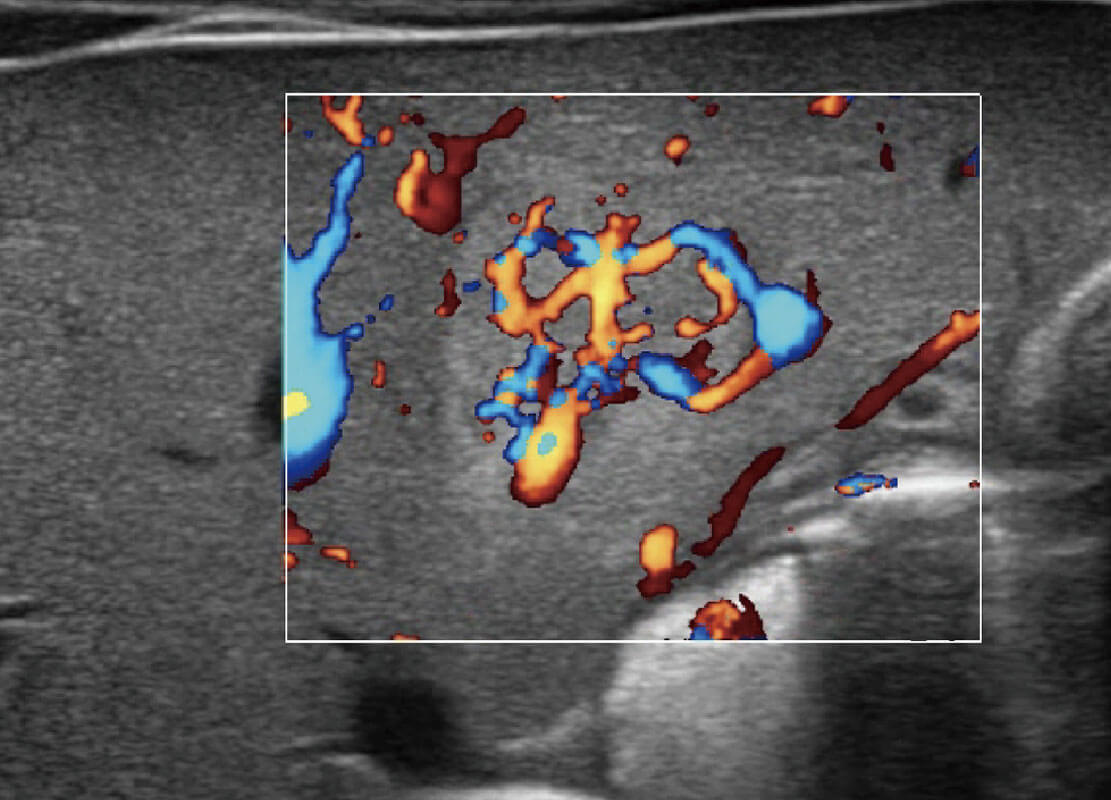

乳腺癌显微血流